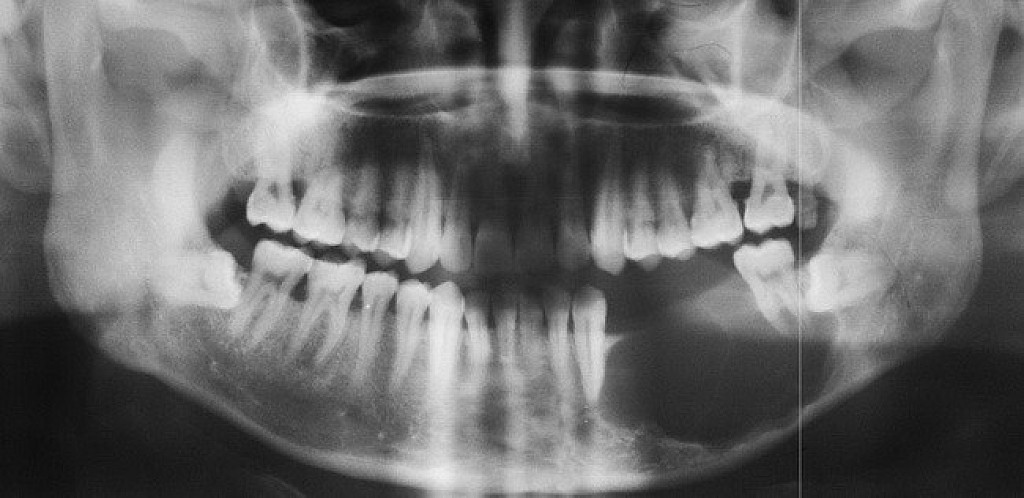

Ameloblastoma is a rare odontogenic tumor, which means it's formed from the normal tissues found in the mouth. Their location is predominately the lower jaw, also known as the mandible. Still, they can be found in the upper jaw or maxilla as well. Sometimes, ameloblastomas are located in the soft tissues surrounding the jaws. There is no known cause for this kind of tumor. However, it may be associated with impacted third molars. Ameloblastomas are usually noncancerous (benign), and they generally affect people between 40 and 60 years old.

Ameloblastoma Symptoms and Diagnosis

Ameloblastoma is usually painless, with the only symptom being swelling in the area. It is usually only identified on radiographic examination in a dental office. Early developing lesions do not displace teeth or cause numbness, so the patient may not know a tumor is growing in one of their jawbones. If a potential lesion is identified on a dental radiograph, more elaborate imaging is required. This will include a CAT scan and possibly an MRI. However, the diagnosis cannot be solely determined by imaging. It requires a biopsy to make the final diagnosis. Cysts will sometimes appear similar to the ameloblastoma on the imaging.